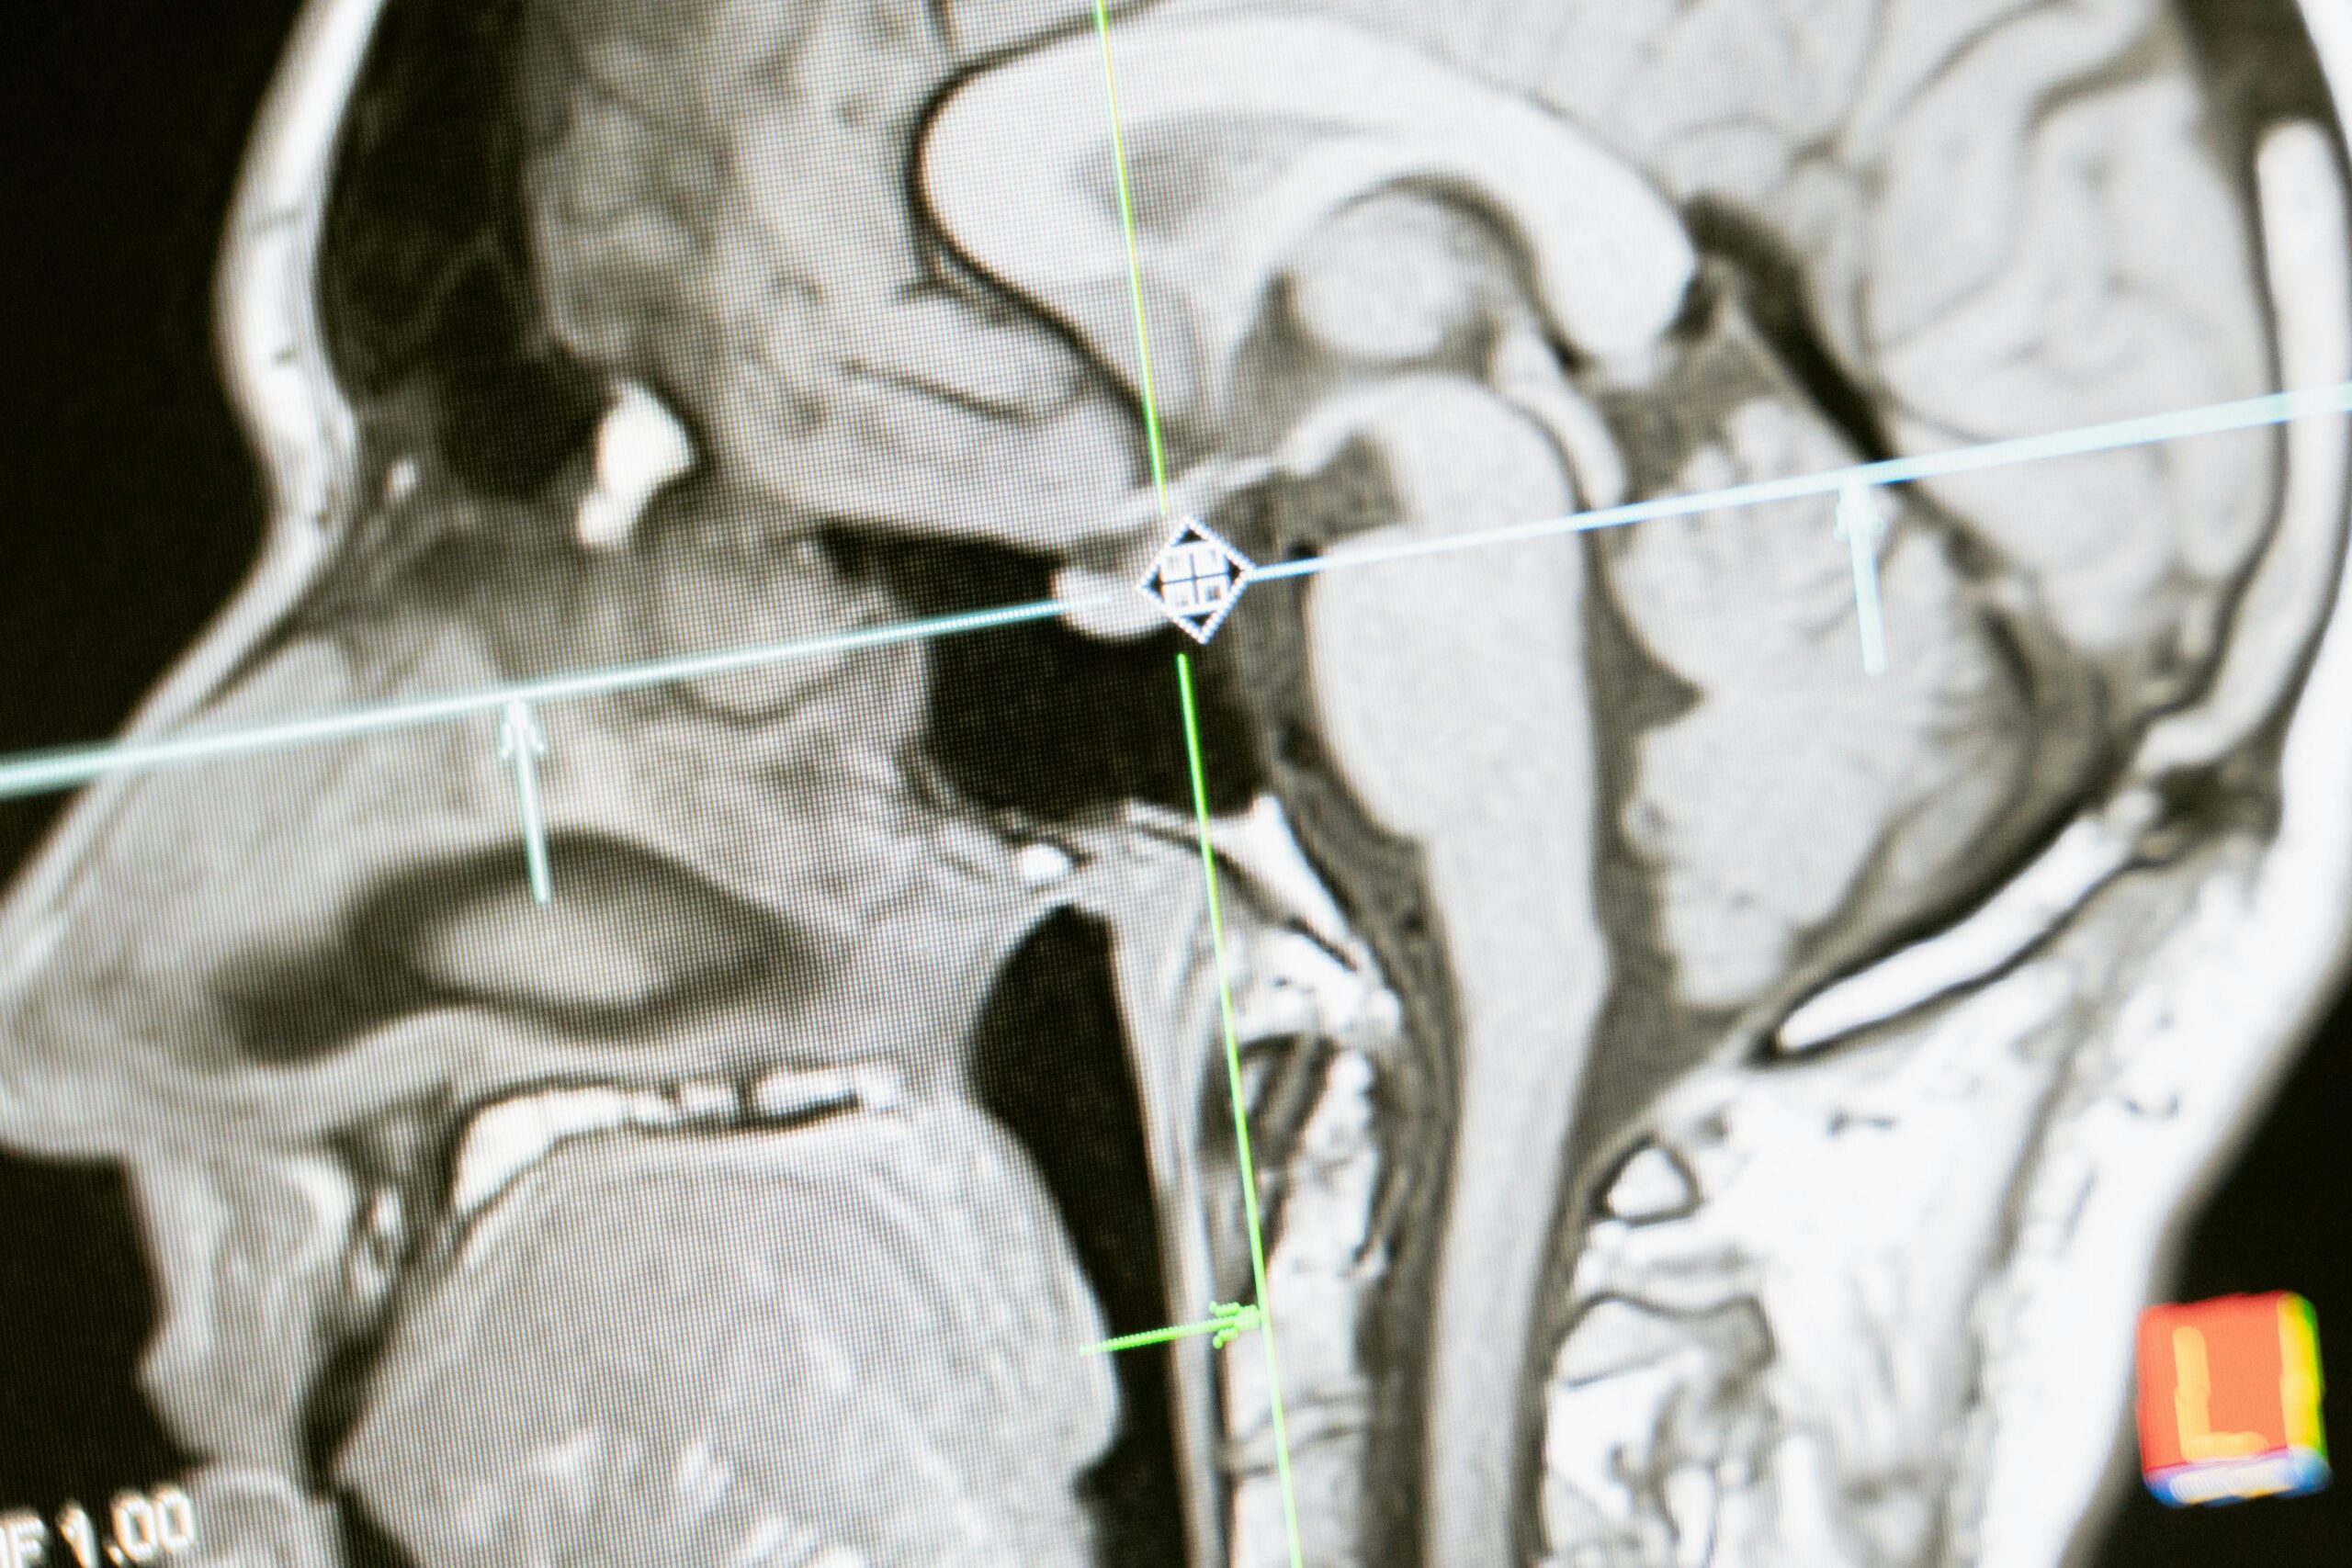

Mentalna svežina i posle 80: Istraživanje otkriva mogućnosti regeneracije mozga

Novo istraživanje pokazuje da žene u poznim godinama mogu zadržati odlično pamćenje zahvaljujući obnovi moždanih ćelija